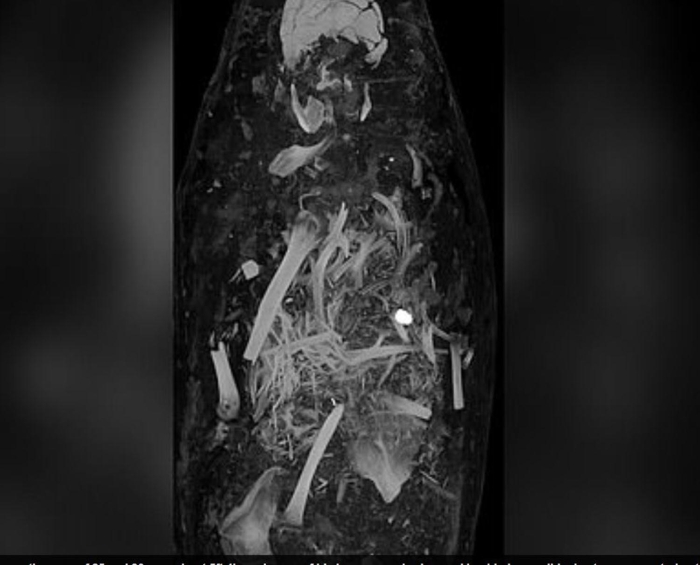

Mısır’da 1615 yılında gömülen üç mumyanın detayları bilgisayarlı tomografi sayesinde ortaya çıktı.Yirmili yaşlarda bir erkek, otuzlu yaşlarda bir kadın ve 17-19 yaşları arasında bir genç kıza ait olan mumyaların, alçı kaplı tabutların içerisinde muhafaza ediliyor. Bilimadamlarının bilgisayarlı tomografi ile incelediği mumyaların tüm organlarıyla birlikte mücevher ve altın sikkelerle gömüldükleri ortaya çıktı. Araştırmacılar, incelemelere göre, söz konusu üç kişinin de sağlık problemleri nedeniyle erken yaşta öldüklerini belirtti.